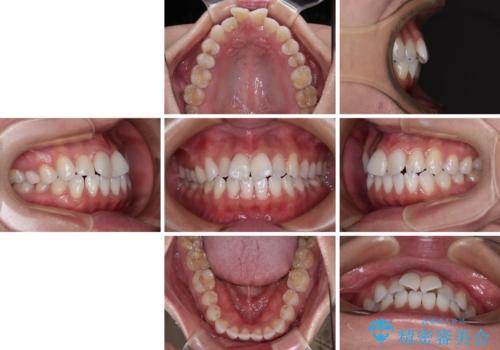

捻れた前歯を楽して改善 ワイヤー装置での非抜歯矯正

- 30代女性

- クリアブラケット

- 1年1ヶ月

- 上下前歯のデコボコを気にして来院された患者様です。

ワイヤー矯正でもマウスピース矯正でも可能でしたが、短期間で、自身の手を煩わせることなく治療を行いたいとのことで、ワイヤー装置にて矯正治療を行うこととしました。